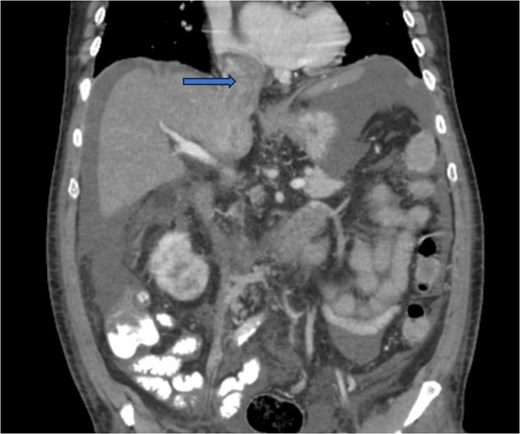

Diagnostic imaging began with a chest X-ray that indicated bilateral pleural effusions. An abdominal ultrasound detected a 4.6 × 4.2 × 4.3 cm echogenic lesion in the right hepatic lobe. Further imaging with a computed tomography (CT) scan of the chest, abdomen, and pelvis revealed a large mass originating from the posterior aspect of the right mid-kidney consistent with RCC (Fig. 1). The mass associated with thrombus extended into the renal sinus and collecting system, traveled along the right renal vein to the inferior vena cava (IVC), and projected into the right atrium (Figs 2 and 3). During hospitalization, bilateral lower extremity pain led to the diagnosis of bilateral deep vein thromboses via duplex venous ultrasound. Echocardiography showed normal left ventricular ejection fraction, impaired diastolic filling, mildly increased ventricular wall thickness, and an echogenic mass extending from the right atrium into the IVC consistent with the tumor thrombus.

CT chest abdomen and pelvis with contrast showing tumor thrombus is seen within the IVC extending over a long distance from the level of the renal vein cephalad into the right atrium.